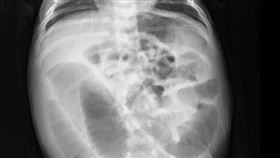

她腹部傳呱呱聲 照X光驚見「灌香腸」

肚子有時候會發出一些「咕咕」聲響,是腸子蠕動的聲音,...